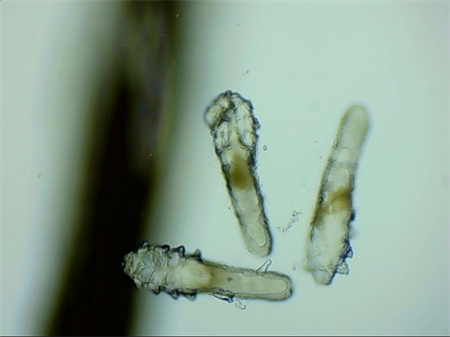

這就不得不提到眼科醫(yī)生經常使用的螨蟲檢測工具——螨蟲鏡檢。它通過顯微利器,無死角全方位掃描你的睫毛,讓螨蟲無處遁形。

▲螨蟲鏡檢